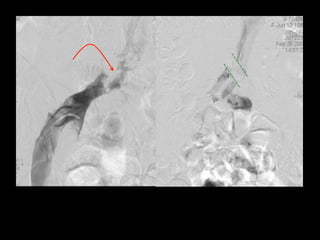

40M prior left arm DVT. Acute pain and swelling of

the left upper arm, rule out DVT.

1:5 dilution (20cc contrast + 80cc NS) @ 3cc/sec. Tourniquet around biceps

region, released 15 sec before initiation of scan.

basilic

Brachial artery

cephalic